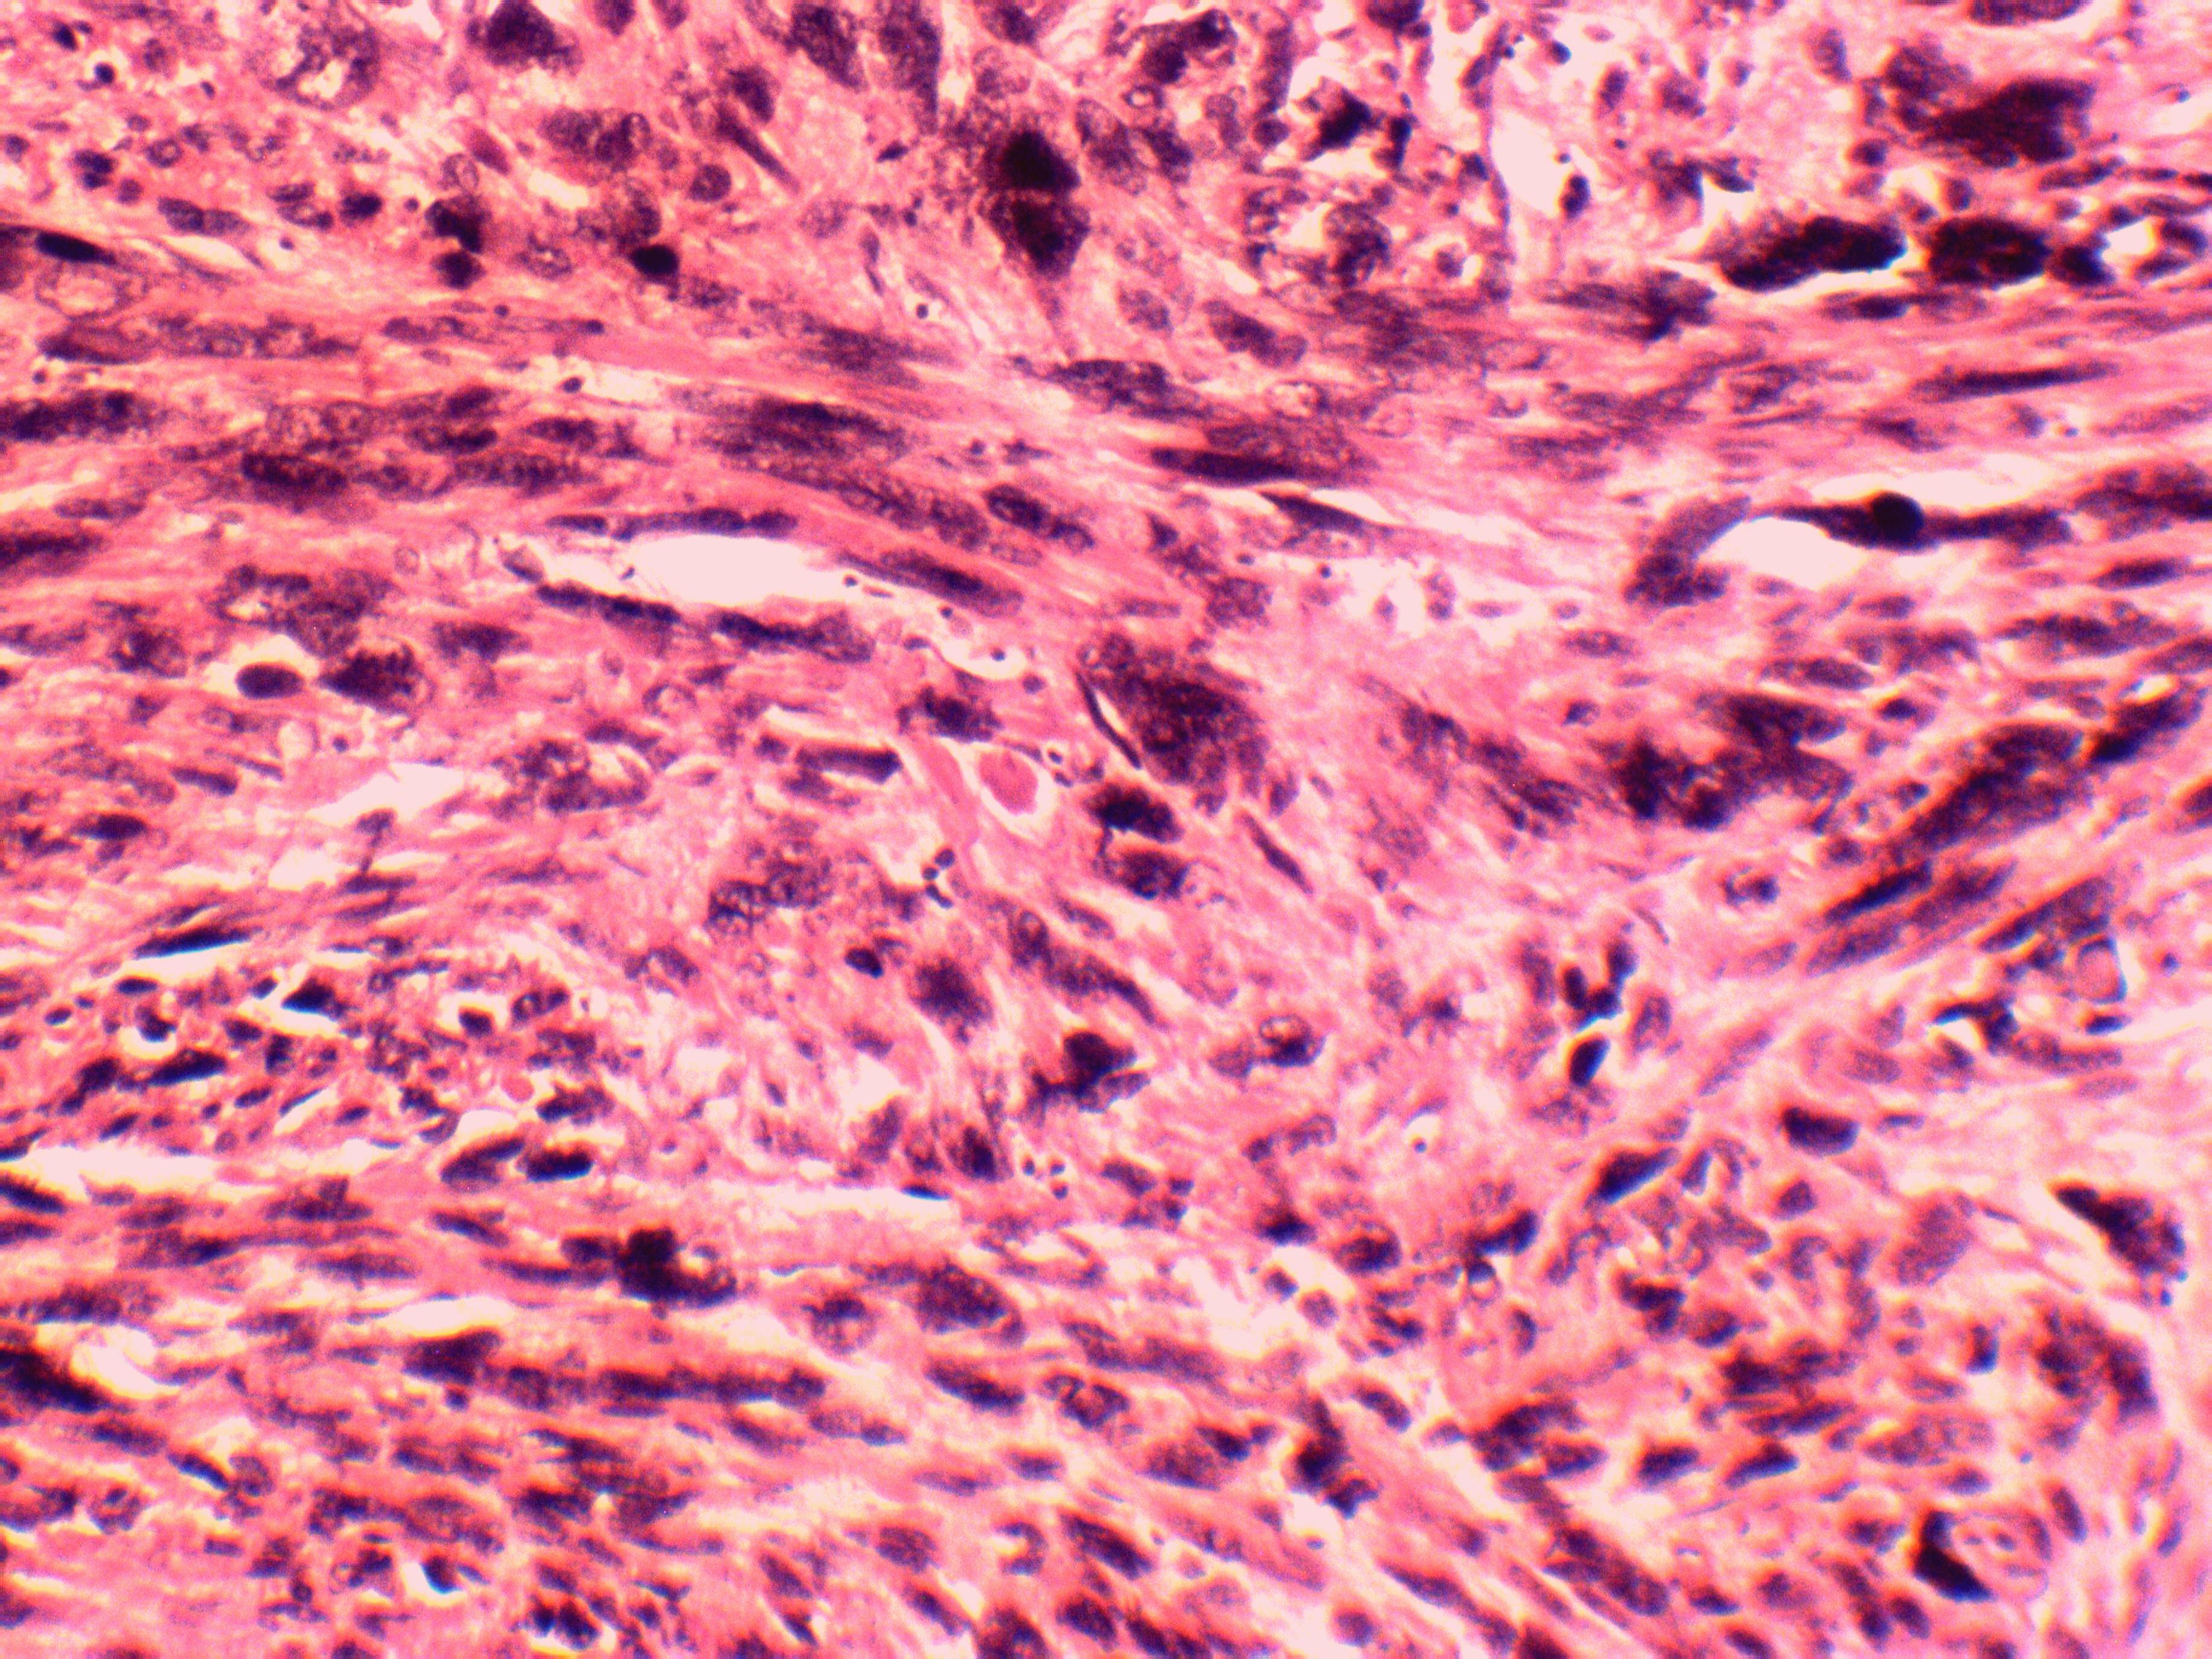

Резюме. Серед злоякісних пухлин матки лейоміосаркома зустрічається в 1-1,3 % випадків. Найчастіше цю пухлину виявляють при дослідженні операційного матеріалу, тому саме гістологічне дослідження є основним методом діагностики лейоміосаркоми матки. При цьому часто виникають труднощі у диференціації цієї пухлини та її доброякісного аналога – лейоміоми. У публікації описаний випадок лейоміосаркоми матки у жінки віком 51 р. Детально репрезентовані анамнестичні та клінічні дані, описано динаміку розвитку захворювання. Основну увагу зосереджено на критеріях мікроскопічної діагностики лейоміосаркоми матки. Так, при гістологічному дослідженні операційного матеріалу виявлено суттєві прояви ремоделювання гладких м’язів міометрію. Ядра міоцитів мали ознаки виродливості, набували великих розмірів, ставали гіперхромними, що є індикатором дистрофічних процесів внаслідок невідповідності між кровопостачанням і проліферацією клітин у злоякісній пухлині. Поліморфізм ядер спостерігався дифузно, а не осередково. Окрім того візуалізувалися патологічні мітози, некрози, крововиливи. Описаний випадок із практики акцентує увагу патоморфологів на труднощах гістологічної верифікації лейоміосаркоми і міоми матки.